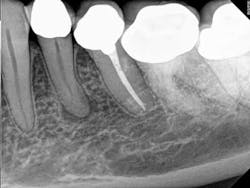

Description of tooth, position, and morphology: Tooth No. 21 diagnosed with pulp necrosis and asymptomatic apical periodontitis. Tooth in normal inclination. This tooth presents with a single root and type IV canal system (one canal bifurcating into two canals).

Pre- and postop comments: Access was made through PFM crown and glidepath established with a Lexicon® #15 Flex SSK hand file. Working length confirmed at 17.0 mm. Final shape was created using the WaveOne® Primary file in the presence of copious sodium hypochlorite.

"This young lady came in to see me with a necrotic No. 21," Dr. Velez said. "Activated irrigation with NaOCl/QMix got me a surprise on the postop (radiograph).

Preop